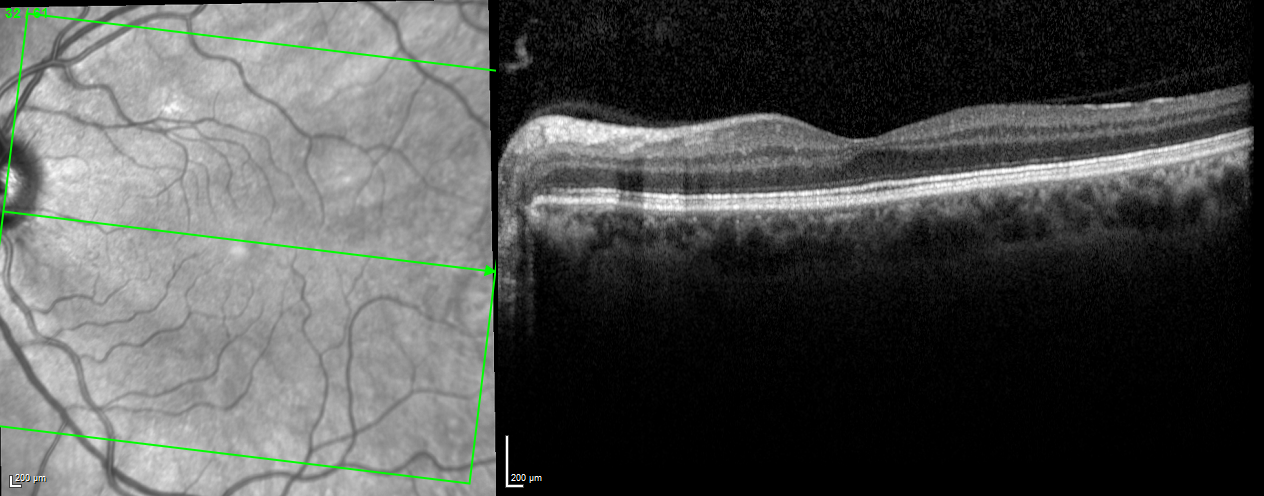

The gold standard for retinal imaging at present is an optical imaging modality called OCT [30]. OCT is non-invasive and is able to acquire high resolution, in-vivo cross-sectional or 3D images from transparent or semi-transparent biological tissues. With the aid of OCT, it has become possible to image retinal anatomy including individual layers such as the ganglion cell layer and diagnose glaucoma before the visual field defects emerge. OCT systems can be classified into time domain based OCT (TD-OCT) and spectral domain based OCT (SD-OCT). The SD-OCT systems have better resolution, are much faster, have higher reproducibility and are more computationally efficient and therefore, SD-OCT has become the gold standard for imaging of the retinal and the optic nerve head [29]. An example of a retinal OCT cross section is shown in Fig. 1.